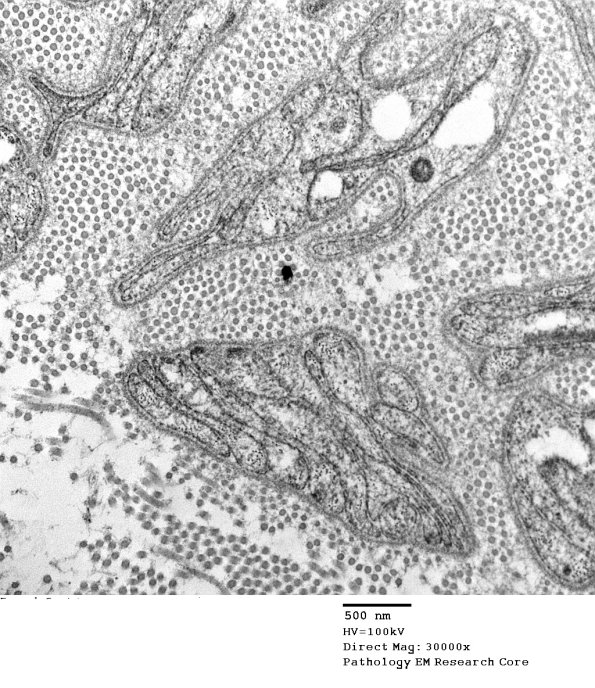

These images show the pathologic substrate in this case which is nearly complete loss of axons with numerous bands of Büngner. (electron micrographs)